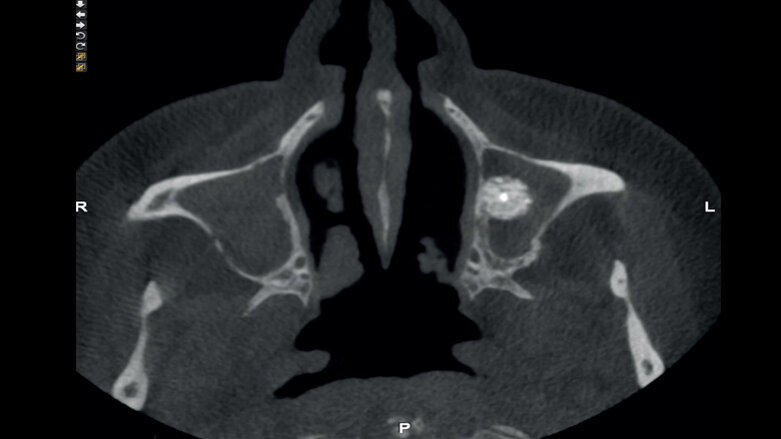

Figura 1. Sinusitis post-injerto.

Sinusitis postoperatoria

La incidencia de la presencia de sinusitis postoperatoria varía en función de los autores y se encuentra entre el 3 y el 14%. Los síntomas más comunes pueden incluir fístulas, dolor, inflamación, obstrucción nasal, dehiscencia del colgajo y secreción purulenta. El aumento de la presión intrasinusal puede ser un factor secundario que puede dar como resultado el bloqueo del drenaje sinusal.

La presencia de sinusitis aguda puede poner en peligro la supervivencia del implante y del injerto. El tratamiento médico con descongestivos y antibióticos puede ser una solución en aquellos pacientes con una predisposición a la sinusitis.